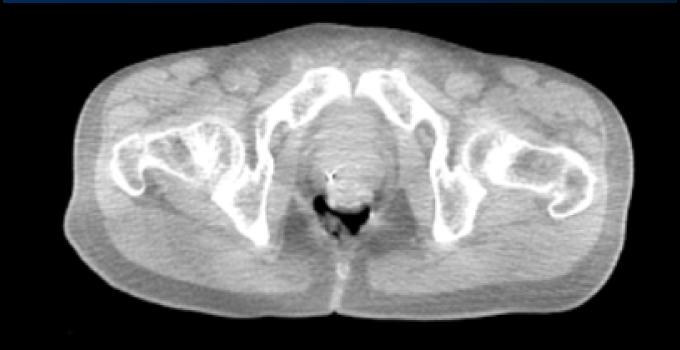

SpaceOAR Vue Hydrogel in different image modalities

kV Cone-beam CT image (first fraction).

kV Cone-beam Computed Tomography image (first fraction)*

*Jeff Michalski, M.D. [2020]. Permission granted by Washington University Image.